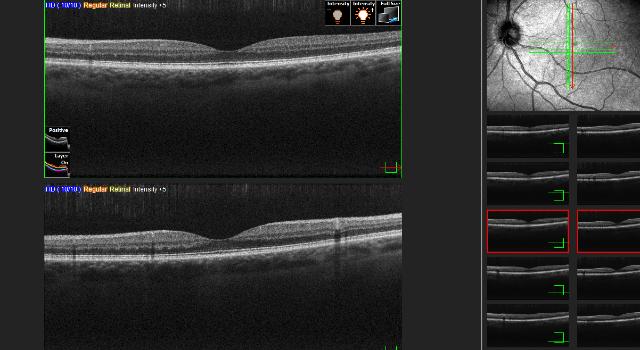

ebovis is the first practice in the world to offer comprehensive eye examinations on a purely instrumental basis. These examinations are systematically standardized and are evaluated independently by individual specialist doctors, leading to an increase in quality and cost savings of 20 to 30 %.

- Objective examinations through instrumental diagnostics.

- High precision thanks to systematic processes and quality controls.